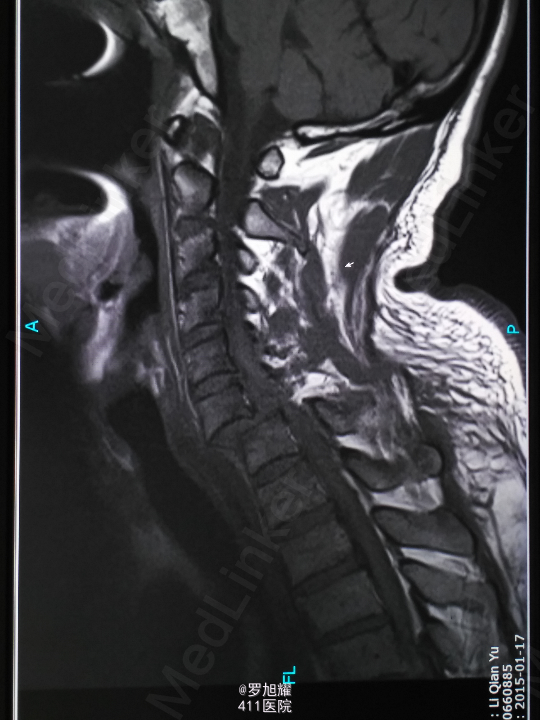

查体:双上肢前臂及以远感觉丧失,躯体自第二肋间平面以下感觉丧失。耸肩可,双侧三角肌、肱二三头肌肌力2级,腕关节屈伸、旋转及各指肌力0级。腱反射阴性,但球海绵体反射已经阳性。影像学检查示颈椎骨折脱位伴颈髓损伤。

诊断:颈6/7骨折脱位伴高位截瘫。处理:立即甲强龙冲击、脱水、保胃、营养神经治疗。首选治疗方案是颅骨牵引复位后前路融合固定,较后路稳定,出血也少,和家属谈话后开始颅骨牵引复位,4kg起步,每半小时增加1kg直至14kg,调整颈椎屈伸位,再加用手法牵引仍不能复位。改用备选方案,急诊行后路切开减压撬拨复位内固定,术后瘫痪症状部分改善。随访3月双上肢前臂及手部感觉恢复,仅双手掌尺侧及小指感觉障碍,双侧三角肌、肱二三头肌肌力4-5级,腕关节屈伸、旋转肌力左侧3级,右侧3-4级,但各指肌力仍0级。